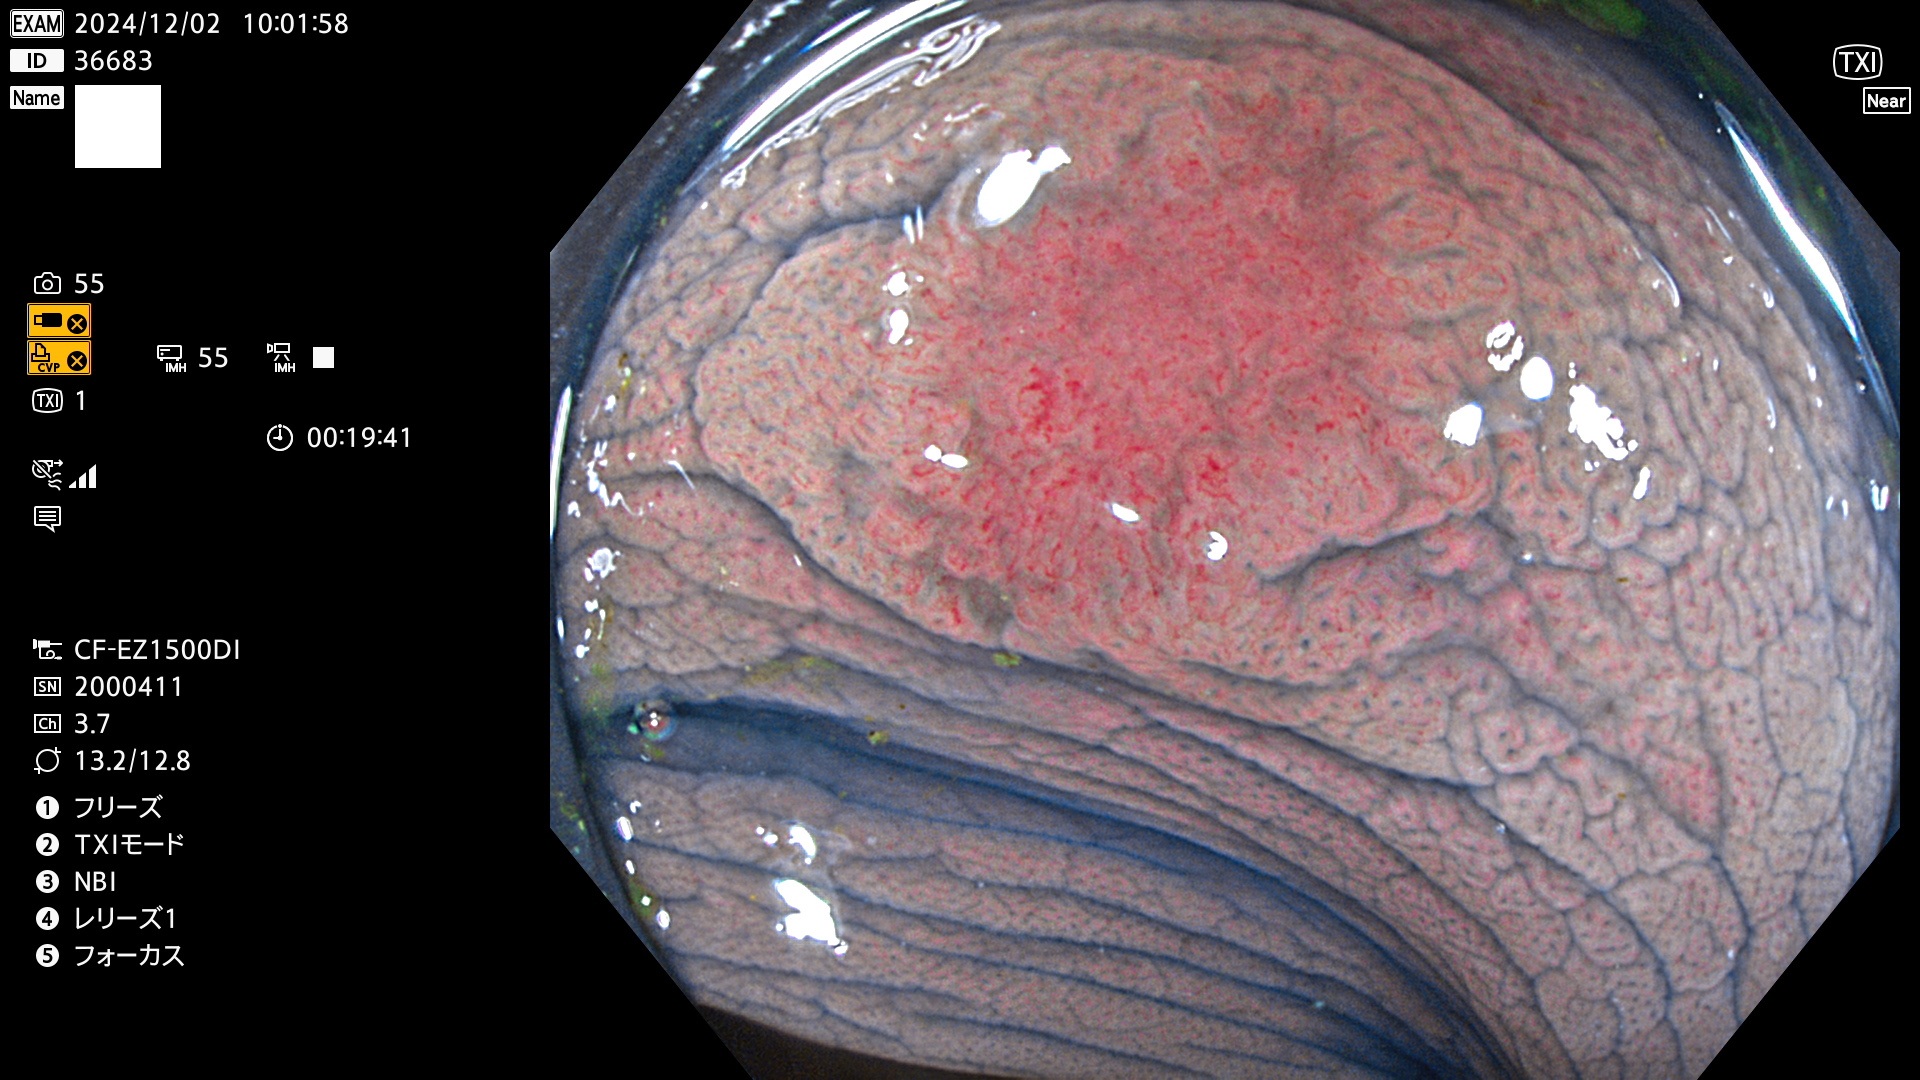

今週のUb、Uc型腺腫

完全に平坦な物をUb、陥凹している物をUcと呼びます。最も発見が難しく危険な病変です。

毎週の検査(木・金・土・日)に発見されたUb、Uc型・腺腫を、その週の日曜の夜にUPし1週間、提示します。

抽出の対象期間 2024年11月28日〜12月2日の5日間(60件の検査)9件 (9/60=15%)